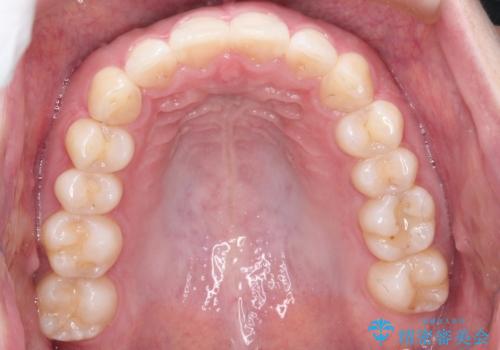

初診時の歯並びの状態としては、下顎前歯に及ぶの中等度のがたつき(叢生)があり、前歯が深く噛みこんでいる状態でした。

抜歯は行わず歯列弓の拡大やディスキング(歯と歯の間の隙間を作る処置)を行い叢生を改善しました。